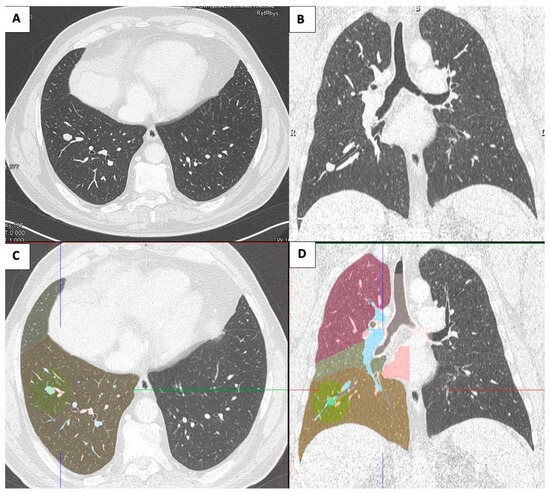

2.2. Case 2